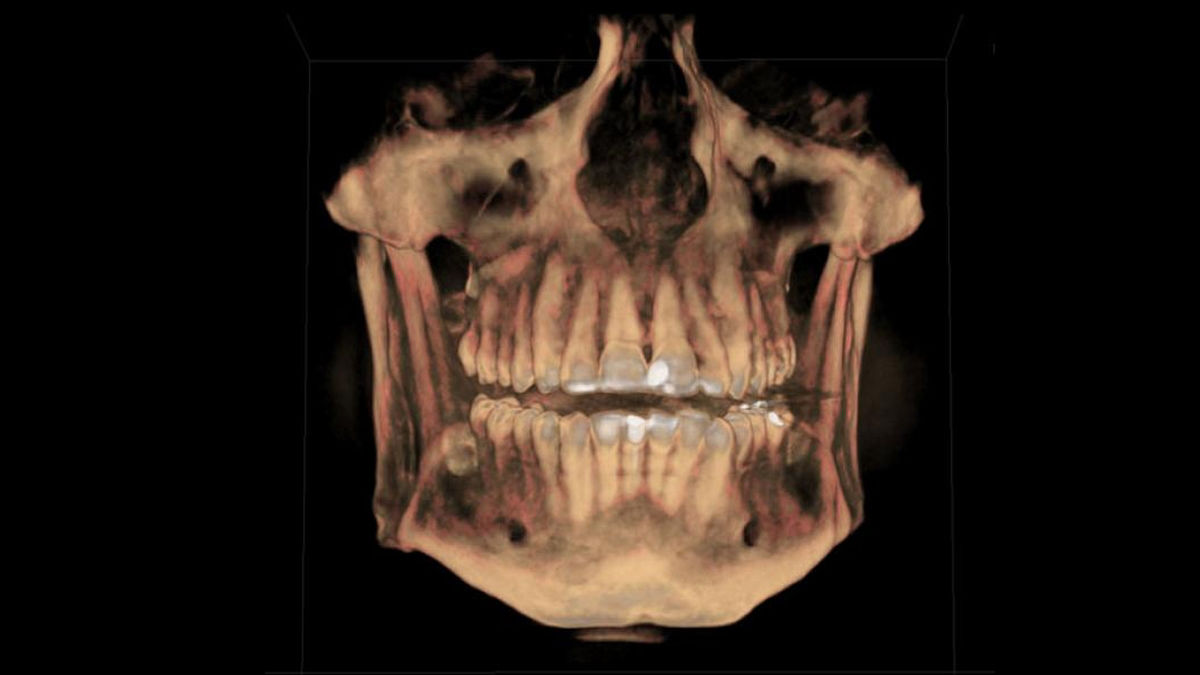

Software de reconstrucción MARS

Los objetos radiopacos, como los metales, causan interferencias en la captación de imagen. El software MARS reconoce automáticamente y reduce estos objetos, ayudando en el diagnóstico sin necesidad de realizar una segunda tomografía.